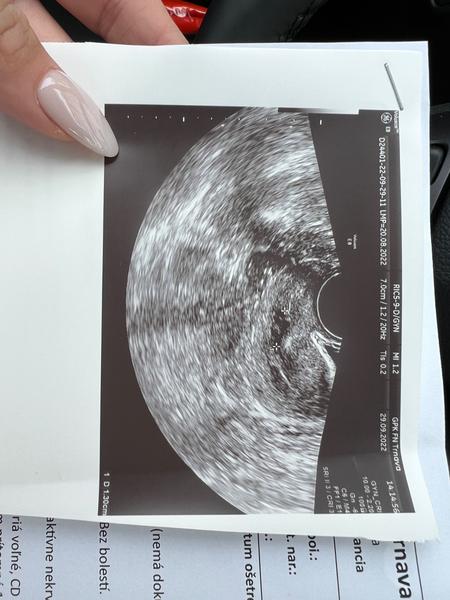

Vidíte tam niečo?

Ahojte baby dnws ok bola na sone lebo som začala krvácať a lekár mi povedal že mám nízko položenú placentu máte skúsenosť ? Pridávam foto z ultrazvuku

@kikinka123456 ja na tom ultrazvuku nieco vidim...